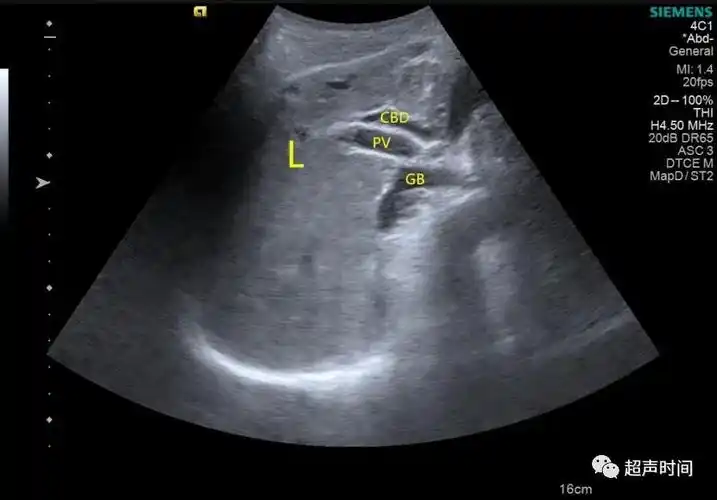

超声入门:急,慢性胆囊炎超声如何诊断?

超声知识胆囊的常见疾病的超声诊断

超声检查如何识别胆总管囊肿